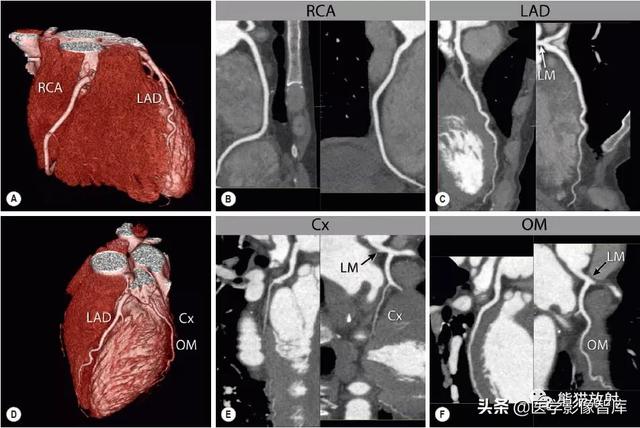

图5 冠状动脉全程显示

右前斜(A)和左前斜(D)的三维容积重建和曲面重建(B,C,E,F)在两个纵向垂直方向显示每支冠状动脉:右冠状动脉(B, RCA) ,左前降支(C, LAD) ,回旋支(E, Cx) 和钝缘支(F, OM) 。注意OM比Cx主干(E)更粗大,这种情况很常见。LM-左主干